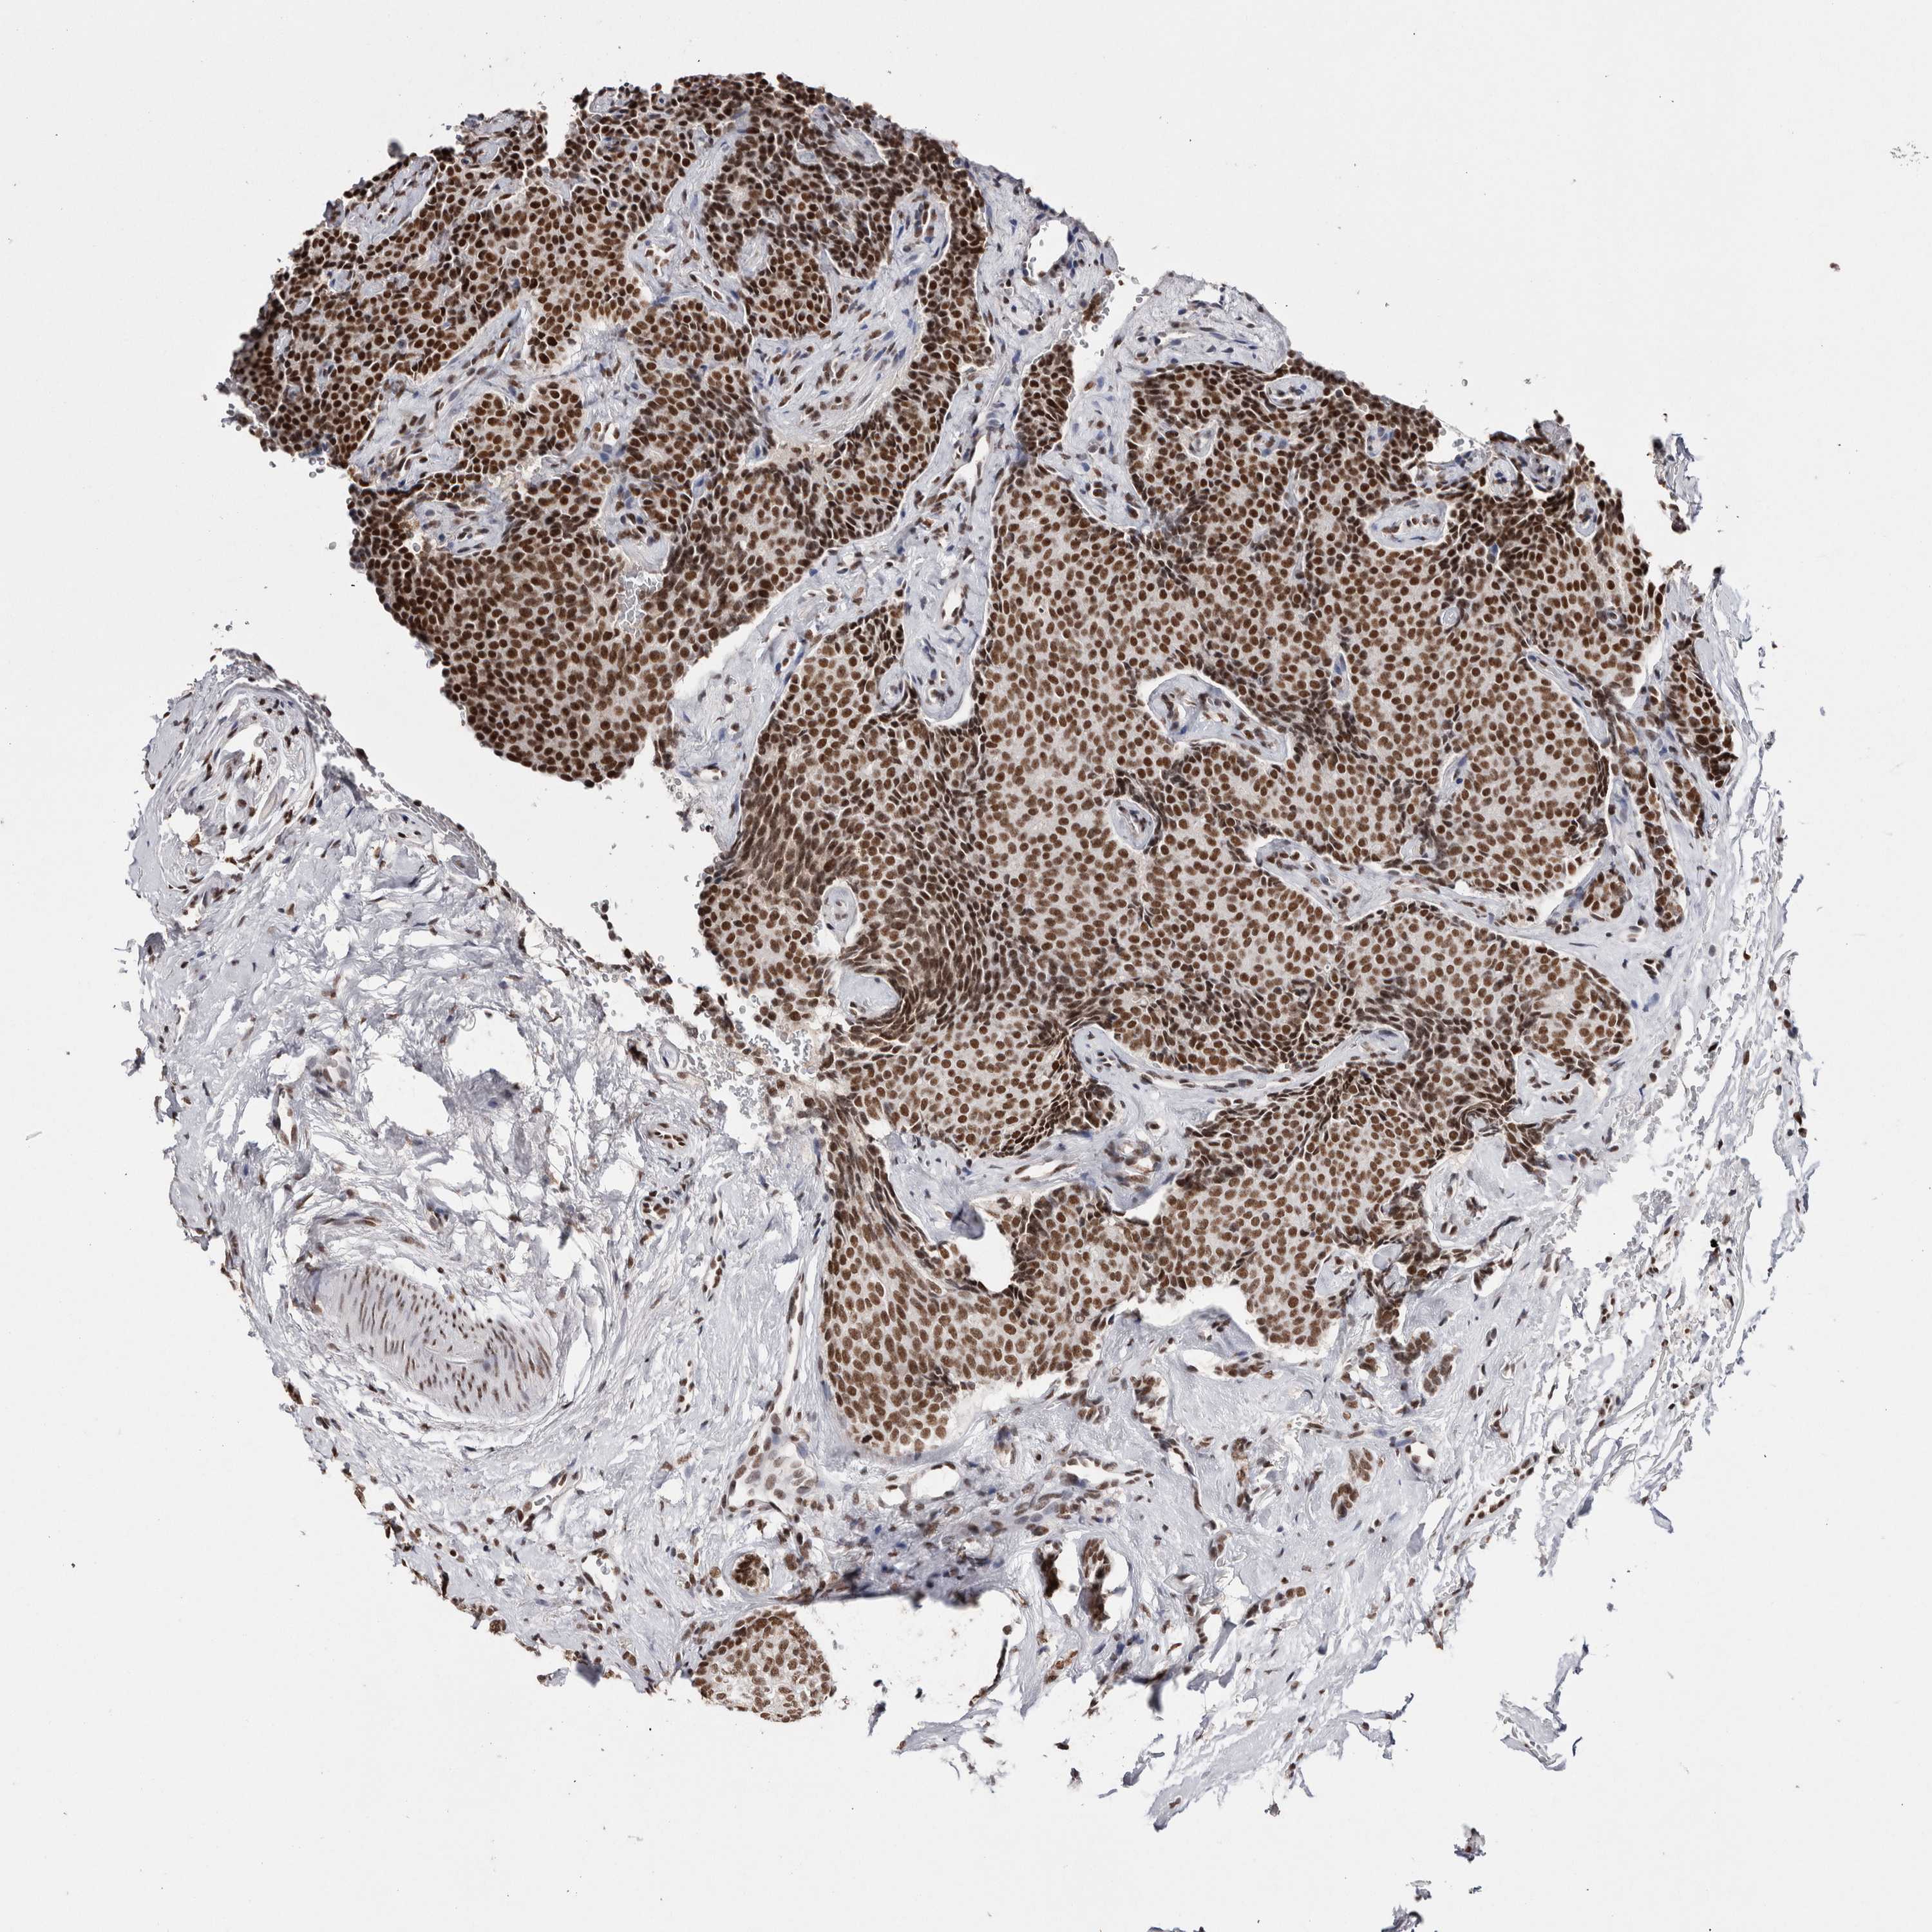

SMC1A

• SMC1A

CANCER BREAST CANCER Show tissue menu

Breast cancer

Human cancer